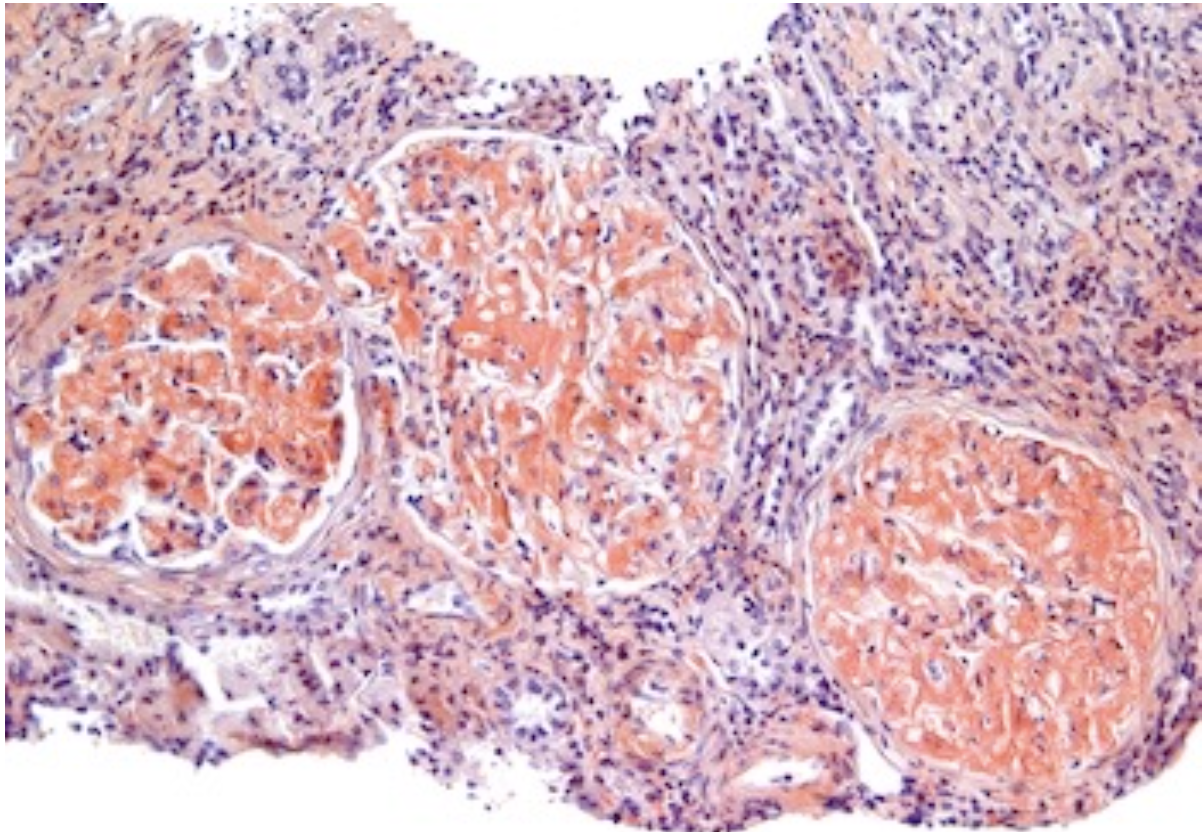

What condition is this lesion characteristic of and what is it?

Capsular drop lesion

Represents leakage of plasma proteins from the damaged capillaries